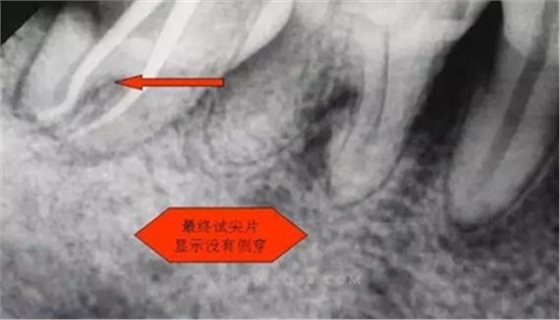

1.拍片基本可以確定遠(yuǎn)中頰側(cè)根管是一個融合根管,也就是常見的C型根管,粗大的根管口是扁形,根管同樣呈扇貝型,根尖孔粗大。而且在根管中上段較粗大,插針拍片后遠(yuǎn)中顯示根管有側(cè)穿的可能,但是通過內(nèi)窺鏡顯示是沒有任何側(cè)穿點,也沒有滲血和患者有疼痛現(xiàn)象。這個病例告訴我們,有時候做根管治療,為了把根管做通和預(yù)備到位,必要的牙體組織去除是可以的,后期可以用冠修復(fù)來彌補(bǔ),如果不去除,本病例的根管治療,根充時可能會面臨充填不嚴(yán)密,從而導(dǎo)致根管治療的失敗,這是不可取的。

6.本病例,由于連接近遠(yuǎn)中2個根管的融合區(qū)頰舌徑過于狹窄,在x線片上顯示不清,而唯一能表現(xiàn)的是近遠(yuǎn)中分離的2個獨立的根管,將K銼放置到頰側(cè)根管內(nèi),有時在x線片上表現(xiàn)出根分叉處可能穿孔,這也是C型根管在x線上的重要特征。